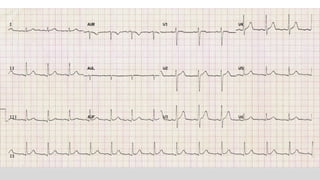

This document discusses various cases of collapse and syncope. It defines collapse as transient loss of consciousness with loss of postural tone and full recovery. Syncope is defined as loss of postural tone with or without loss of consciousness and full recovery. It then discusses the multiple potential causes of collapse and syncope including toxicological, cardiac conduction abnormalities, structural cardiac issues, autonomic dysfunction and more. It then goes through 9 case examples, discussing important questions to ask, potential tests and interventions for each case.